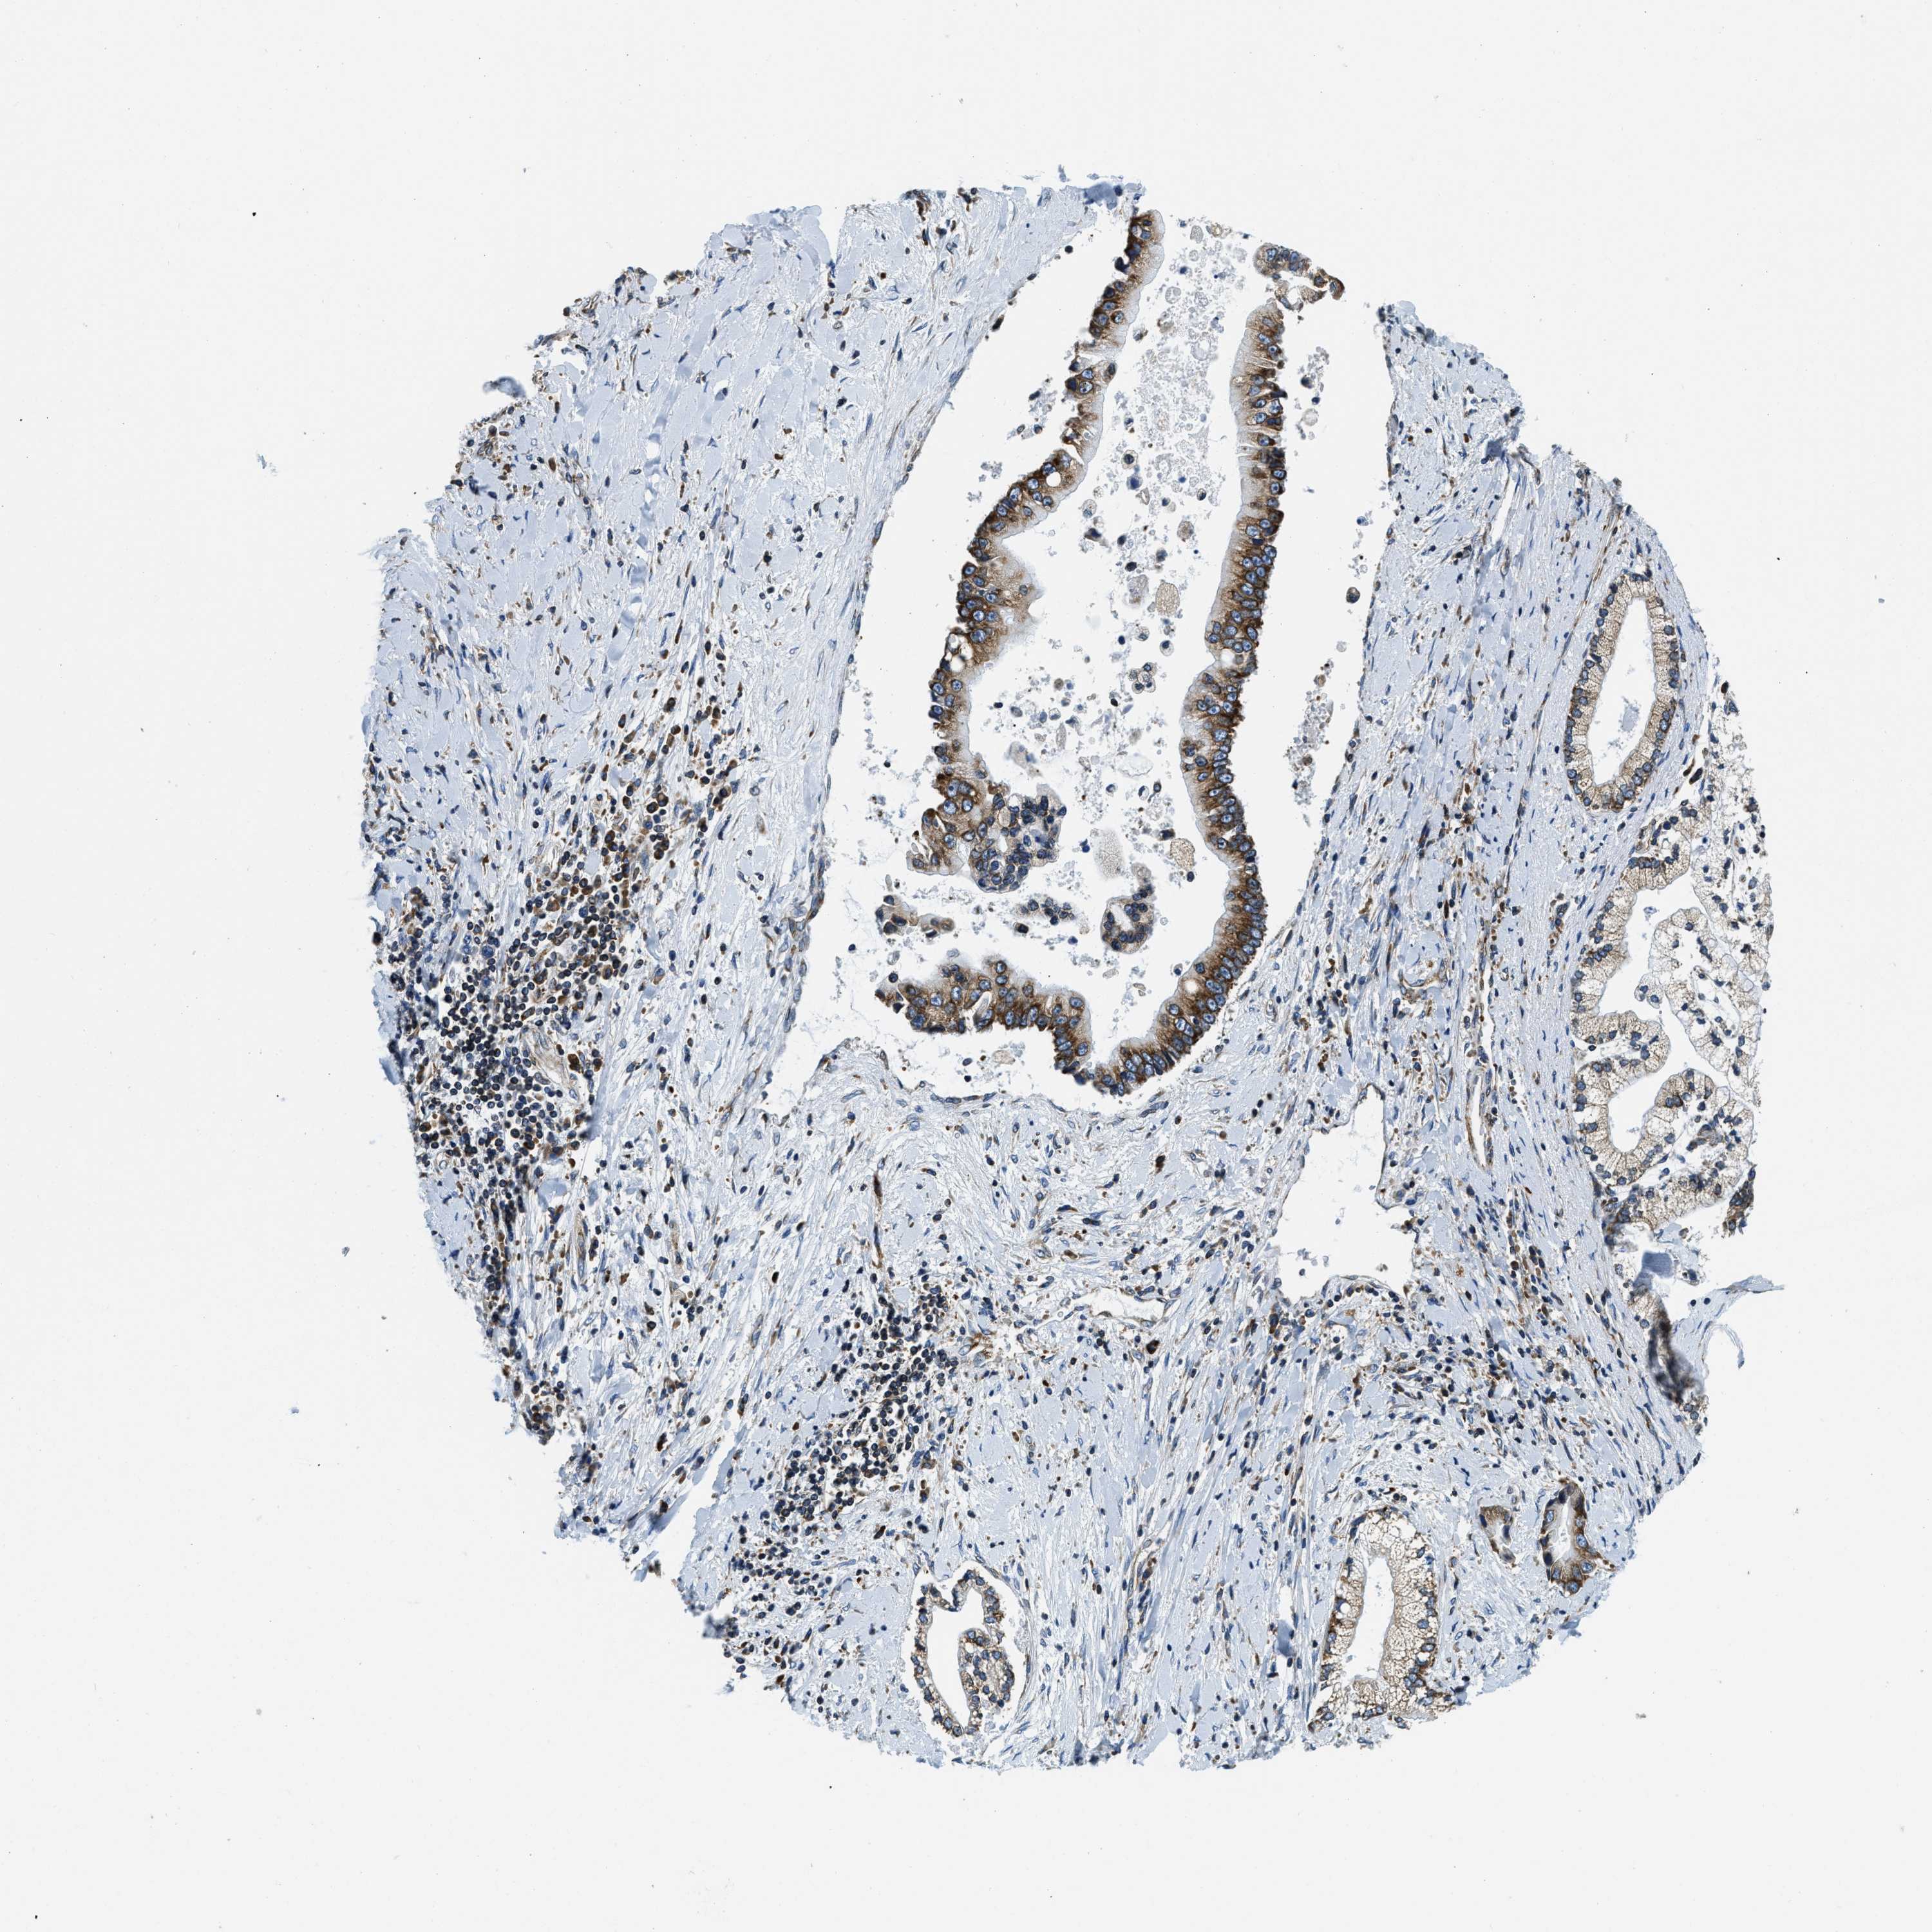

LIVER CANCER - Protein expressioni

A mouse-over function shows sample information and annotation data. Click on an image to view it in a full screen mode. Samples can be filtered based on level of antibody staining by selecting one or several of the following categories: high, medium, low and not detected. The assay and annotation is described here.

Note that samples used for immunohistochemistry by the Human Protein Atlas do not correspond to samples in the TCGA dataset.

Antibody stainingi

Antibody staining in the annotated cell types in the current human tissue is reported as not detected, low, medium, or high, based on conventional immunohistochemistry profiling in selected tissues. This score is based on the combination of the staining intensity and fraction of stained cells.

Each image is clickable and will lead to virtual microscopy that enables deeper exploration of all samples and also displays staining intensity scores, fraction scores and subcellular localization as well as patient and tissue information for each sample.

Antibody HPA019698

Staining

High

Medium

Low

Not detected

Intensity

Strong

Moderate

Weak

Negative

Quantity

>75%

75%-25%

<25%

None

Location

Nuclear

Cytoplasmic/membranous

Cytoplasmic/membranous,nuclear

Cholangiocarcinoma

Carcinoma, Hepatocellular, NOS